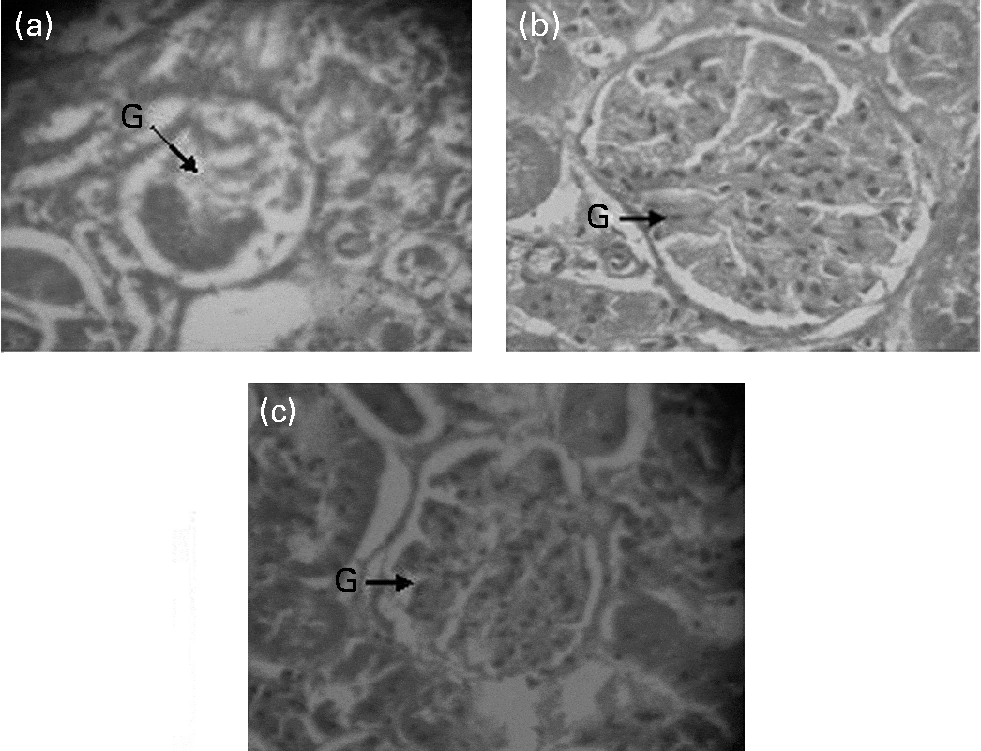

(A) Millet seeds appearance of the lungs due to miliary tuberculous Millet Seed Ganglion Diagnosis can be made clinically with a firm and well. Operative findings of “rice bodies, millet seeds, or melon seeds” are highly suggestive of tuberculous tenosynovitis. Rice bodies in wrist ganglia are highly suggestive of tuberculous tenosynovitis. Six patients with tb of the hand. In the case of seed ganglia the base is. Tuberculous tenosynovitis, formerly known as compound palmar. Millet Seed Ganglion.